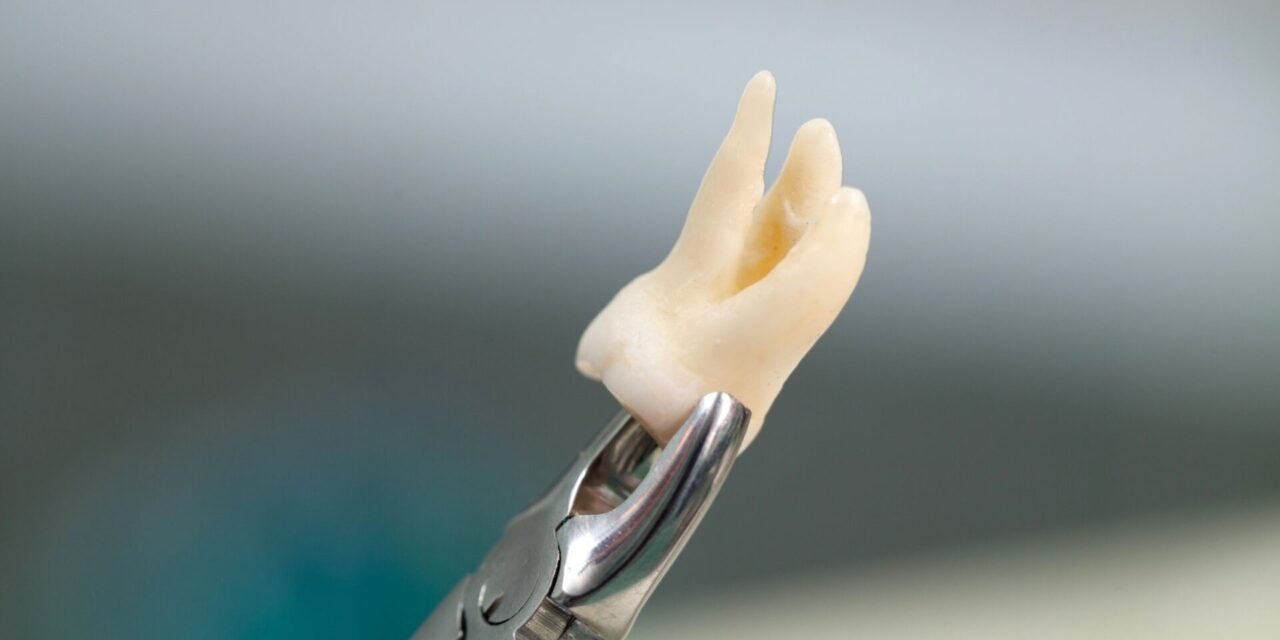

La decisión de realizar una extracción de cordales debe ser estrictamente clínica. No siempre es necesario intervenir si la muela está sana y bien alineada. Sin embargo, la extracción es prioritaria cuando existe falta de espacio evidente.

También recomendamos la cirugía si la muela interfiere con la salud de los tejidos blandos. En casos de ortodoncia invisible, a veces es necesario ganar espacio para alinear los dientes. Un especialista debe valorar la trayectoria de erupción para evitar daños futuros.

La cirugía oral para extraer cordales es uno de los procedimientos más frecuentes y seguros. Gracias a los avances en anestesia local y sedación, el paciente no siente dolor. En manos expertas, las complicaciones son mínimas y el tiempo de recuperación es corto.

Nuestra trayectoria de 30 años avala protocolos de seguridad extremadamente rigurosos. Utilizamos técnicas de mínima invasión para reducir la inflamación postoperatoria. La planificación digital previa nos permite actuar con una precisión milimétrica, protegiendo los nervios cercanos.